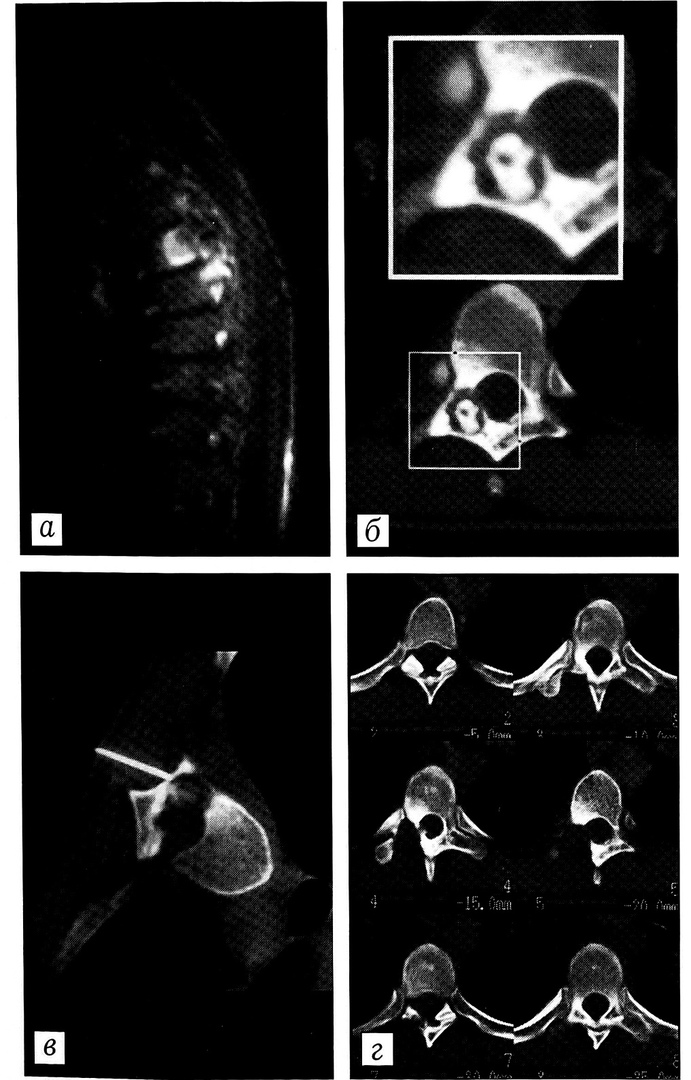

С целью дифференциальной диагностики у 2 больных проводилось контрастирование очага деструкции. У одного из них по результатам контрастного исследования исключен диагноз дистрофической кисты головки левой бедренной кости, у другого подтверждены деструкция дна вертлужной впадины и формирование абсцесса в полости малого таза (рис. 6). У обоих больных диагноз верифицирован морфологическим исследованием материала биопсии, выполненной под контролем КТ.

Рис 6. Больной К. Неспецифический воспалительный процесс в дне левой вертлужной впадины с формированием абсцесса в малом тазе. a — диагностическое компьютерное сканирование; б — введение контрастного вещества с целью дифференциальной диагностики.